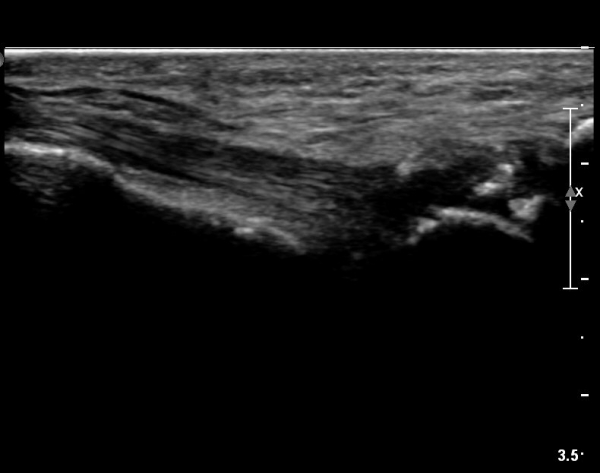

ŽÃËÀÚ¸¦ Á» ´õ ±ÙÀ§ºÎ·Î À̵¿ÇÏ¿© Àåºñ°ñ°ÇÀÇ Á¾´Ü¸é ±ÙÀ§ºÎ ¿µ»óÀ» È®ÀÓÇÔ(»çÁø 4)